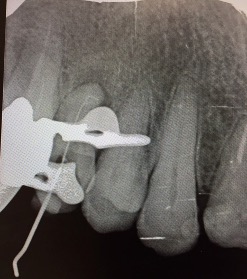

Una corretta terapia canalare con un perfetto sigillo a livello degli apici delle radici è fondamentale. I denti devitalizzati impropriamente possono creare ulteriori problemi che poi andranno a ripercuotersi sulle cure effettuate successivamente come le ricostruzioni e le corone protesiche con conseguente fallimento del piano terapeutico.

Capita spesso di incontrare denti già devitalizzati in maniera impropria che necessitano, seppur asintomatici, di essere ritrattati per evitare che i granulomi infetti visibili radiograficamente si evolvano riassorbendo tutto l’osso sottostante.